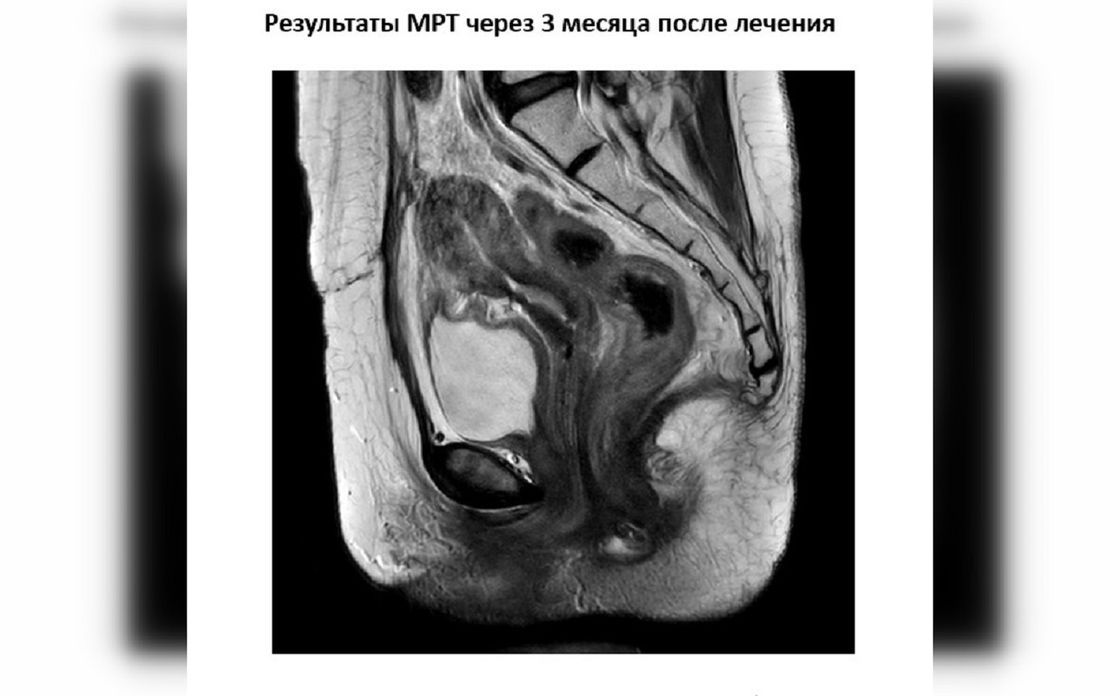

В Национальном научном онкологическом центре 33-летней пациентке с раком шейки матки провели комбинированное лечение, после которого уже через 3 месяца опухоль перестала визуализироваться, об этом сообщили представители онкологического центра.

"После первого этапа мы оцениваем результат на МРТ, определяем остаточный объем опухоли и планируем брахитерапию", — объясняет радиационный онколог ННОЦ Гайни Олжатаева.

В центре применяется МРТ-симулятор 1,5 Тесла, который позволяет значительно повысить точность визуализации опухоли и считается важным стандартом при планировании 3D-брахитерапии. В отличие от компьютерной томографии, она позволяет четче увидеть границы опухоли и точнее рассчитать зону облучения. Дополнительно используется система фиксации пациента, которая помогает сохранять одинаковое положение на всех этапах и обеспечивает точную доставку дозы.

Фото: ННОЦ